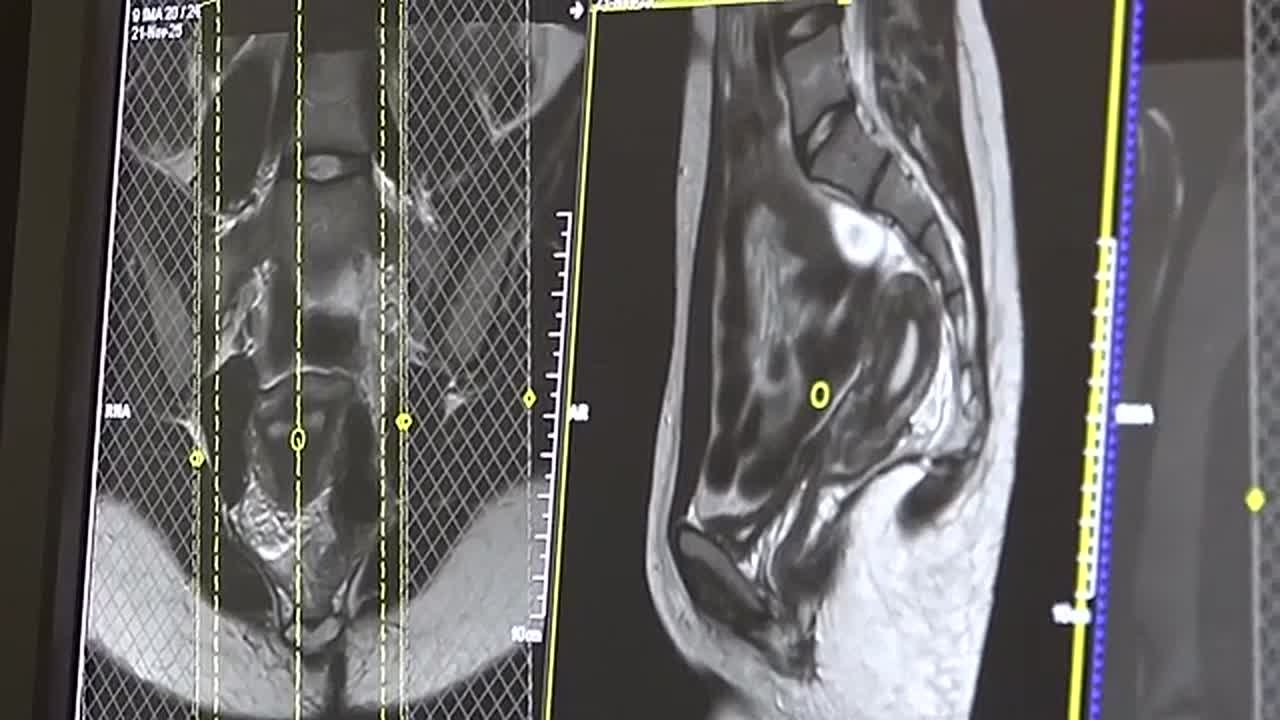

Экскурсию для учеников школы космонавтики провели в Красноярском краевом клиническом центре охраны материнства и детства. Ребятам показали все потаённые уголки медучреждения, рассказали о принципах работы и сложных случаях. Вместе со школьниками по больничным помещениям прошла наша съемочная группа.